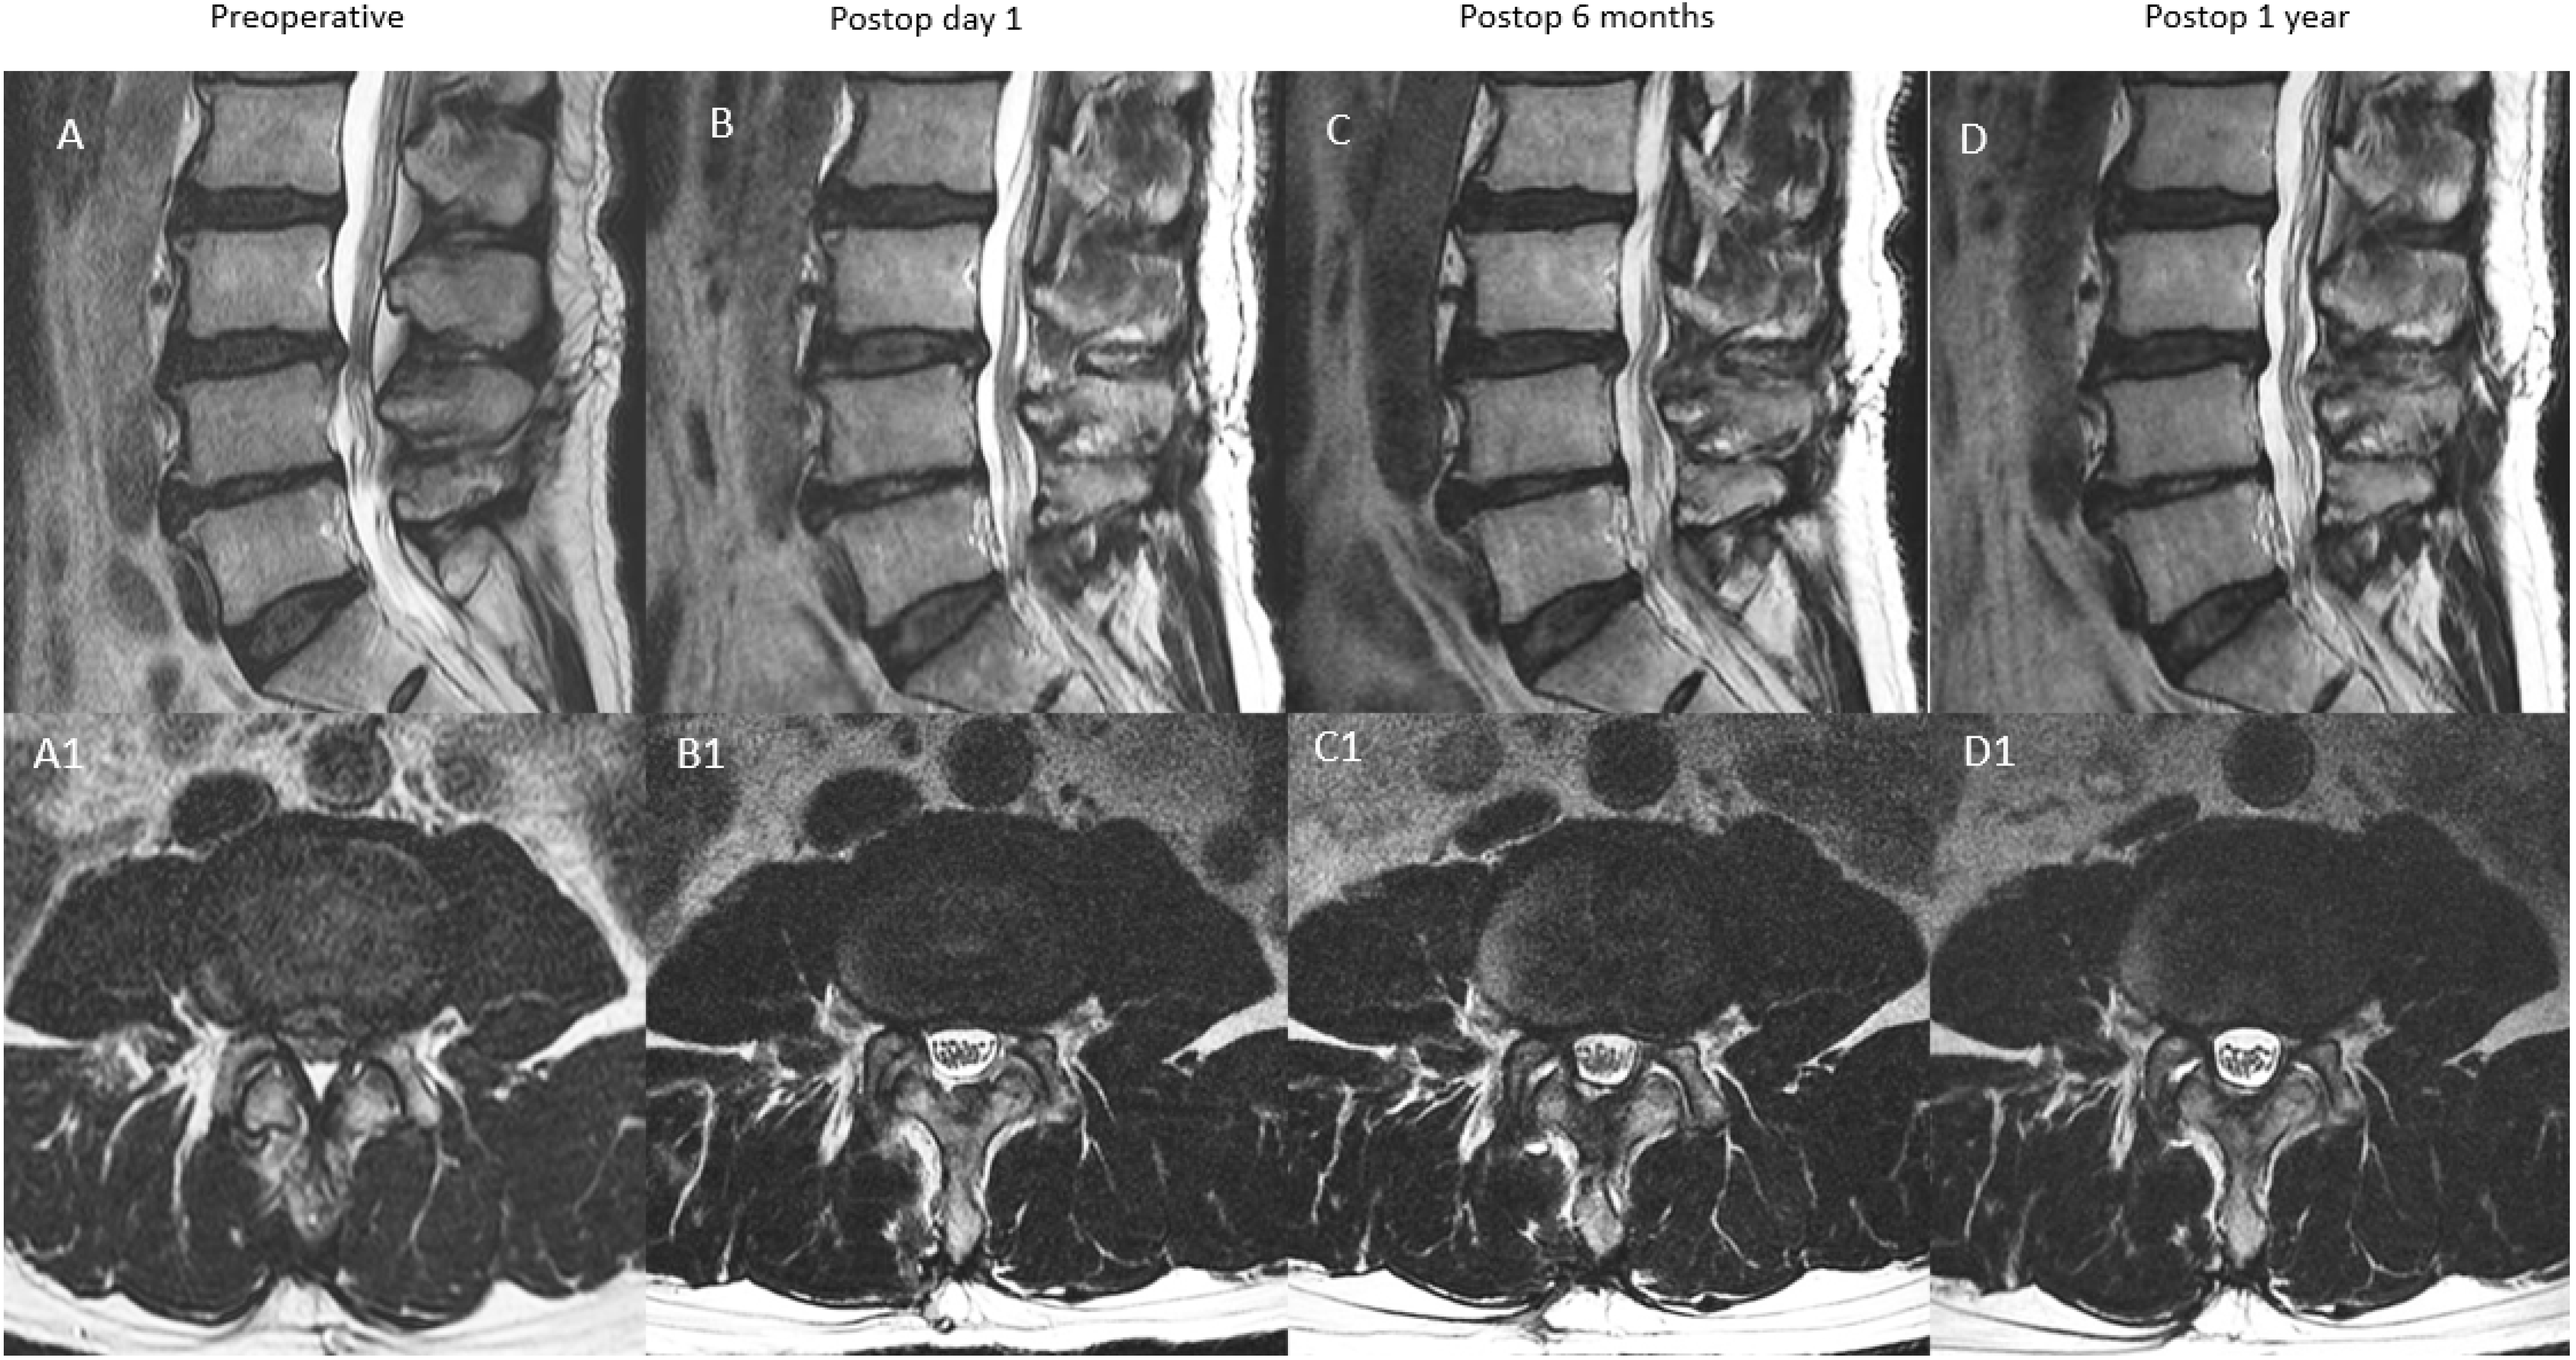

| A: Continuous Type | There is significant decompression with increased spinal canal area on postoperative day one, a modest drop at postoperative 6 months and close to postoperative 6 months value at postoperative one year | X | ≥70% X | 70–90% X (close to postoperative six months value) |

| B: Remodelling Type | There is significant decompression with increased spinal canal area on postoperative day one, a significant drop at postoperative 6 months and modest improvement at one year but less than 90% of the postoperative day one spinal canal area | X | <70% X | 70–90% X |

| C: Expansion Type | There is significant decompression with increased spinal canal area on postoperative day one, a modest drop at postoperative 6 months and significant improvement at one year with more than 90% of the postoperative day one spinal canal area | X | ≥70% X | 90–100% X |

| D: Restenosis Type | There is significant decompression with increased spinal canal area on postoperative day one, a significant drop at postoperative 6 months and minimal improvement at one year with <70% of the postoperative day one spinal canal area | X | <70% X | <70% X |